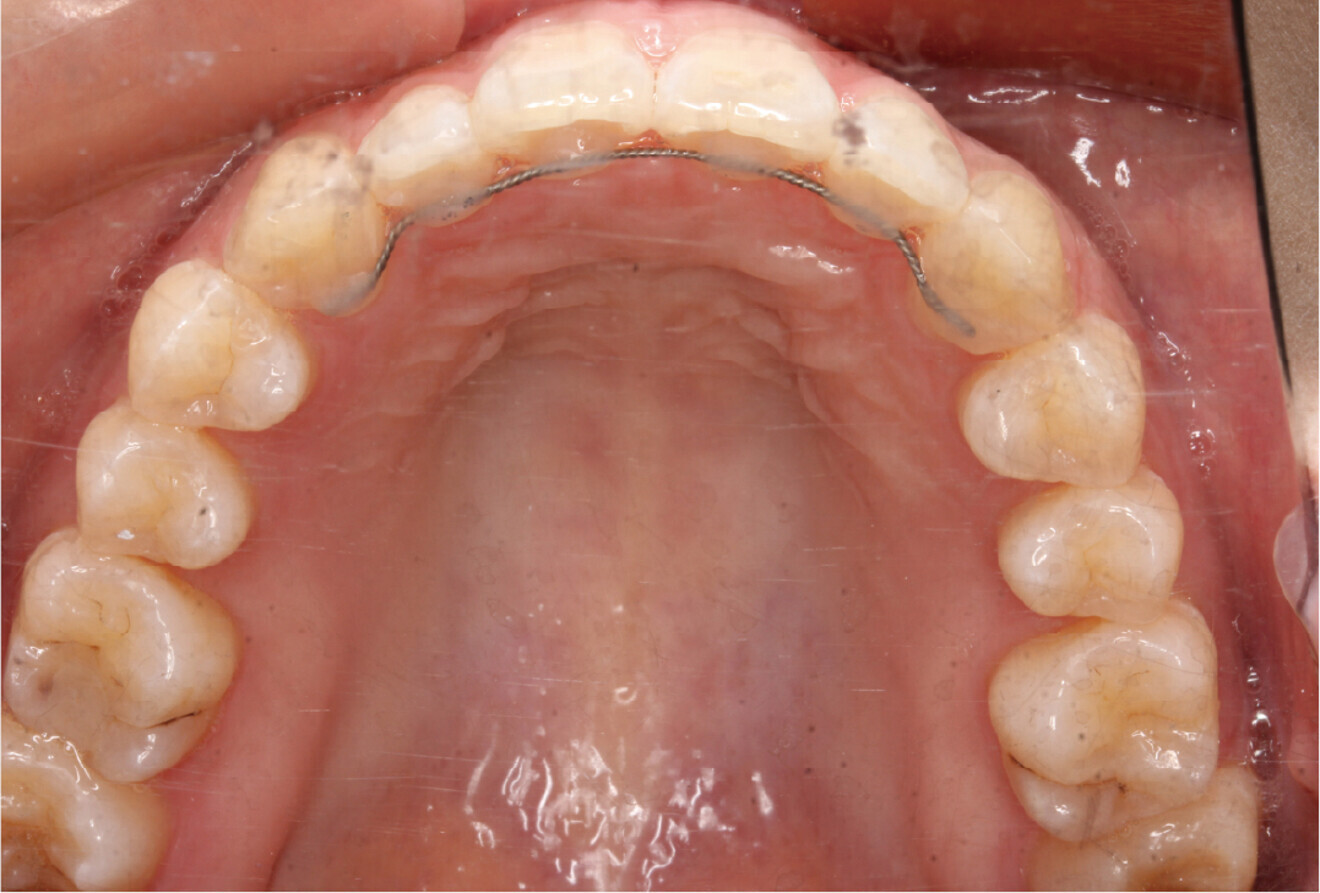

Fig. 4e: Occlusal intra-oral view of the maxilla.